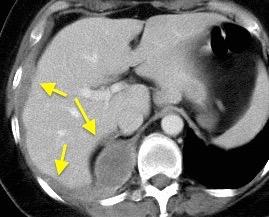

T. mixto de células germinales del testículo izquierdo

Nódulos pulmonares múltiples. (flechas verdes). Masas paratraqueales. (flechas amarillas). Dudoso ensanchamiento retrocrural (flechas negras). sigue….

Ttawfik A et al. Trans-diaphragmatic Pathologies: Anatomical Background and Spread of Disease on cross-sectional Imaging. Current Problems in Diagnostic Radiology. 2021.

T. mixto de células germinales del testículo

izquierdo Metástasis pulmonares. (flechas verdes). Ganglios paratraqueales. (flechas amarillas). Ganglios retroperitoneales (flechas negras)

Tawfik A et al. Trans-diaphragmatic Pathologies: Anatomical Background and Spread of Disease on cross-sectional Imaging. Current Problems in Diagnostic Radiology. 2021.